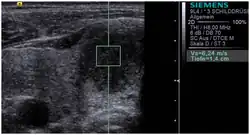

![]() Conventional ultrasonography (lower image) and elastography (supersonic shear imaging; upper image) of papillary thyroid carcinoma, a malignant cancer. The cancer (red) is much stiffer than the healthy tissue. | |